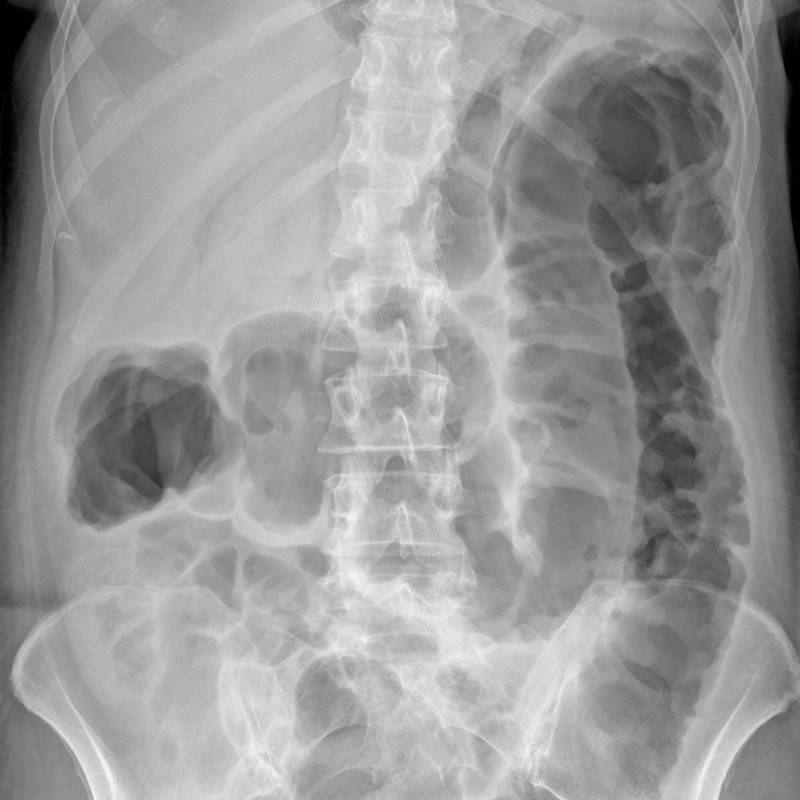

Dalam sesetengah kes, X-Ray boleh digunakan untuk menilai keadaan abdomen, seperti kehadiran gas atau cecair yang tidak normal.

Sinar-X untuk menilai organ dalam perut.